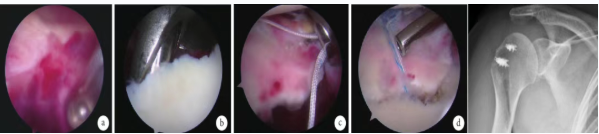

(1)关节镜下手术治疗

关节镜是诊断肩袖损伤的最准确的方法,也是治疗肩袖损伤的一种方式,以往认为适用于中小型肩袖撕裂在,随着肩关节镜技术的发展,医师操作水平的提高,现已无明确界限。对长期保守治疗无效且其他检查方法不易确诊的病例,关节镜具有独特的诊治价值。

①肩峰下减压成形术:其目的就是解除因肩峰下狭窄而导致的撞击综合征,避免肌腱再受撞击,适用于肩峰下间隙狭窄喙肩韧带有骨赘存在的患者,近期有学者报道通过肩峰下减压成形术治疗钙化性肌腱炎获得确切疗效。

②关节镜下肩袖缝合术:关节镜下修补肩袖损伤具有创伤小的优点。